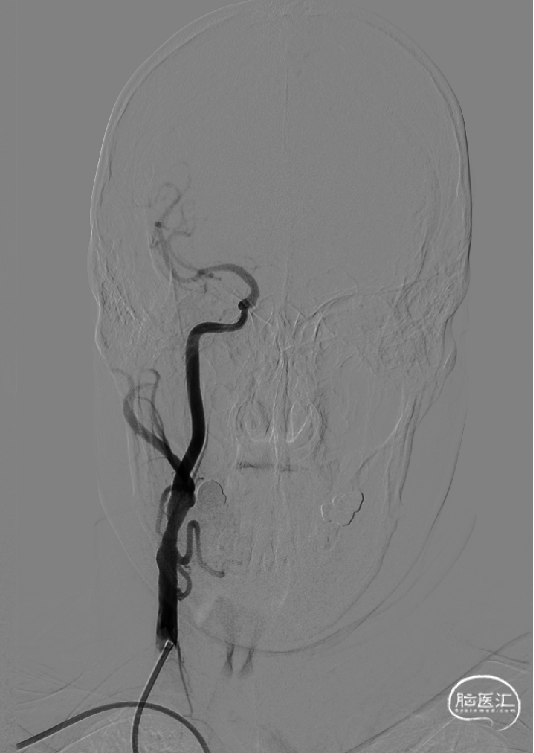

以260cm泥鳅导丝辅助125cm Simmons 2和6F导引导管超选右侧颈总动脉远端,撤出泥鳅导丝及造影管,再次造影可见右侧颈内动脉起始部重度狭窄,狭窄率约80%。

微导丝路图下通过右侧颈内动脉起始部狭窄处至C2段,沿微神途威龙导丝送入Safecer栓塞保护器路图下超选至右侧颈内动脉颈段远段,撤出微导丝,小心释放保护伞,延微导丝送入4.0*30mm球囊超选至右侧颈内动脉狭窄处,12atm快速充盈球囊及回抽,患者心率、血压未见变化,撤出球囊。

沿保护伞导丝将颈动脉支架8*40mm支架小心前移至狭窄处,手推造影确定支架到位良好。